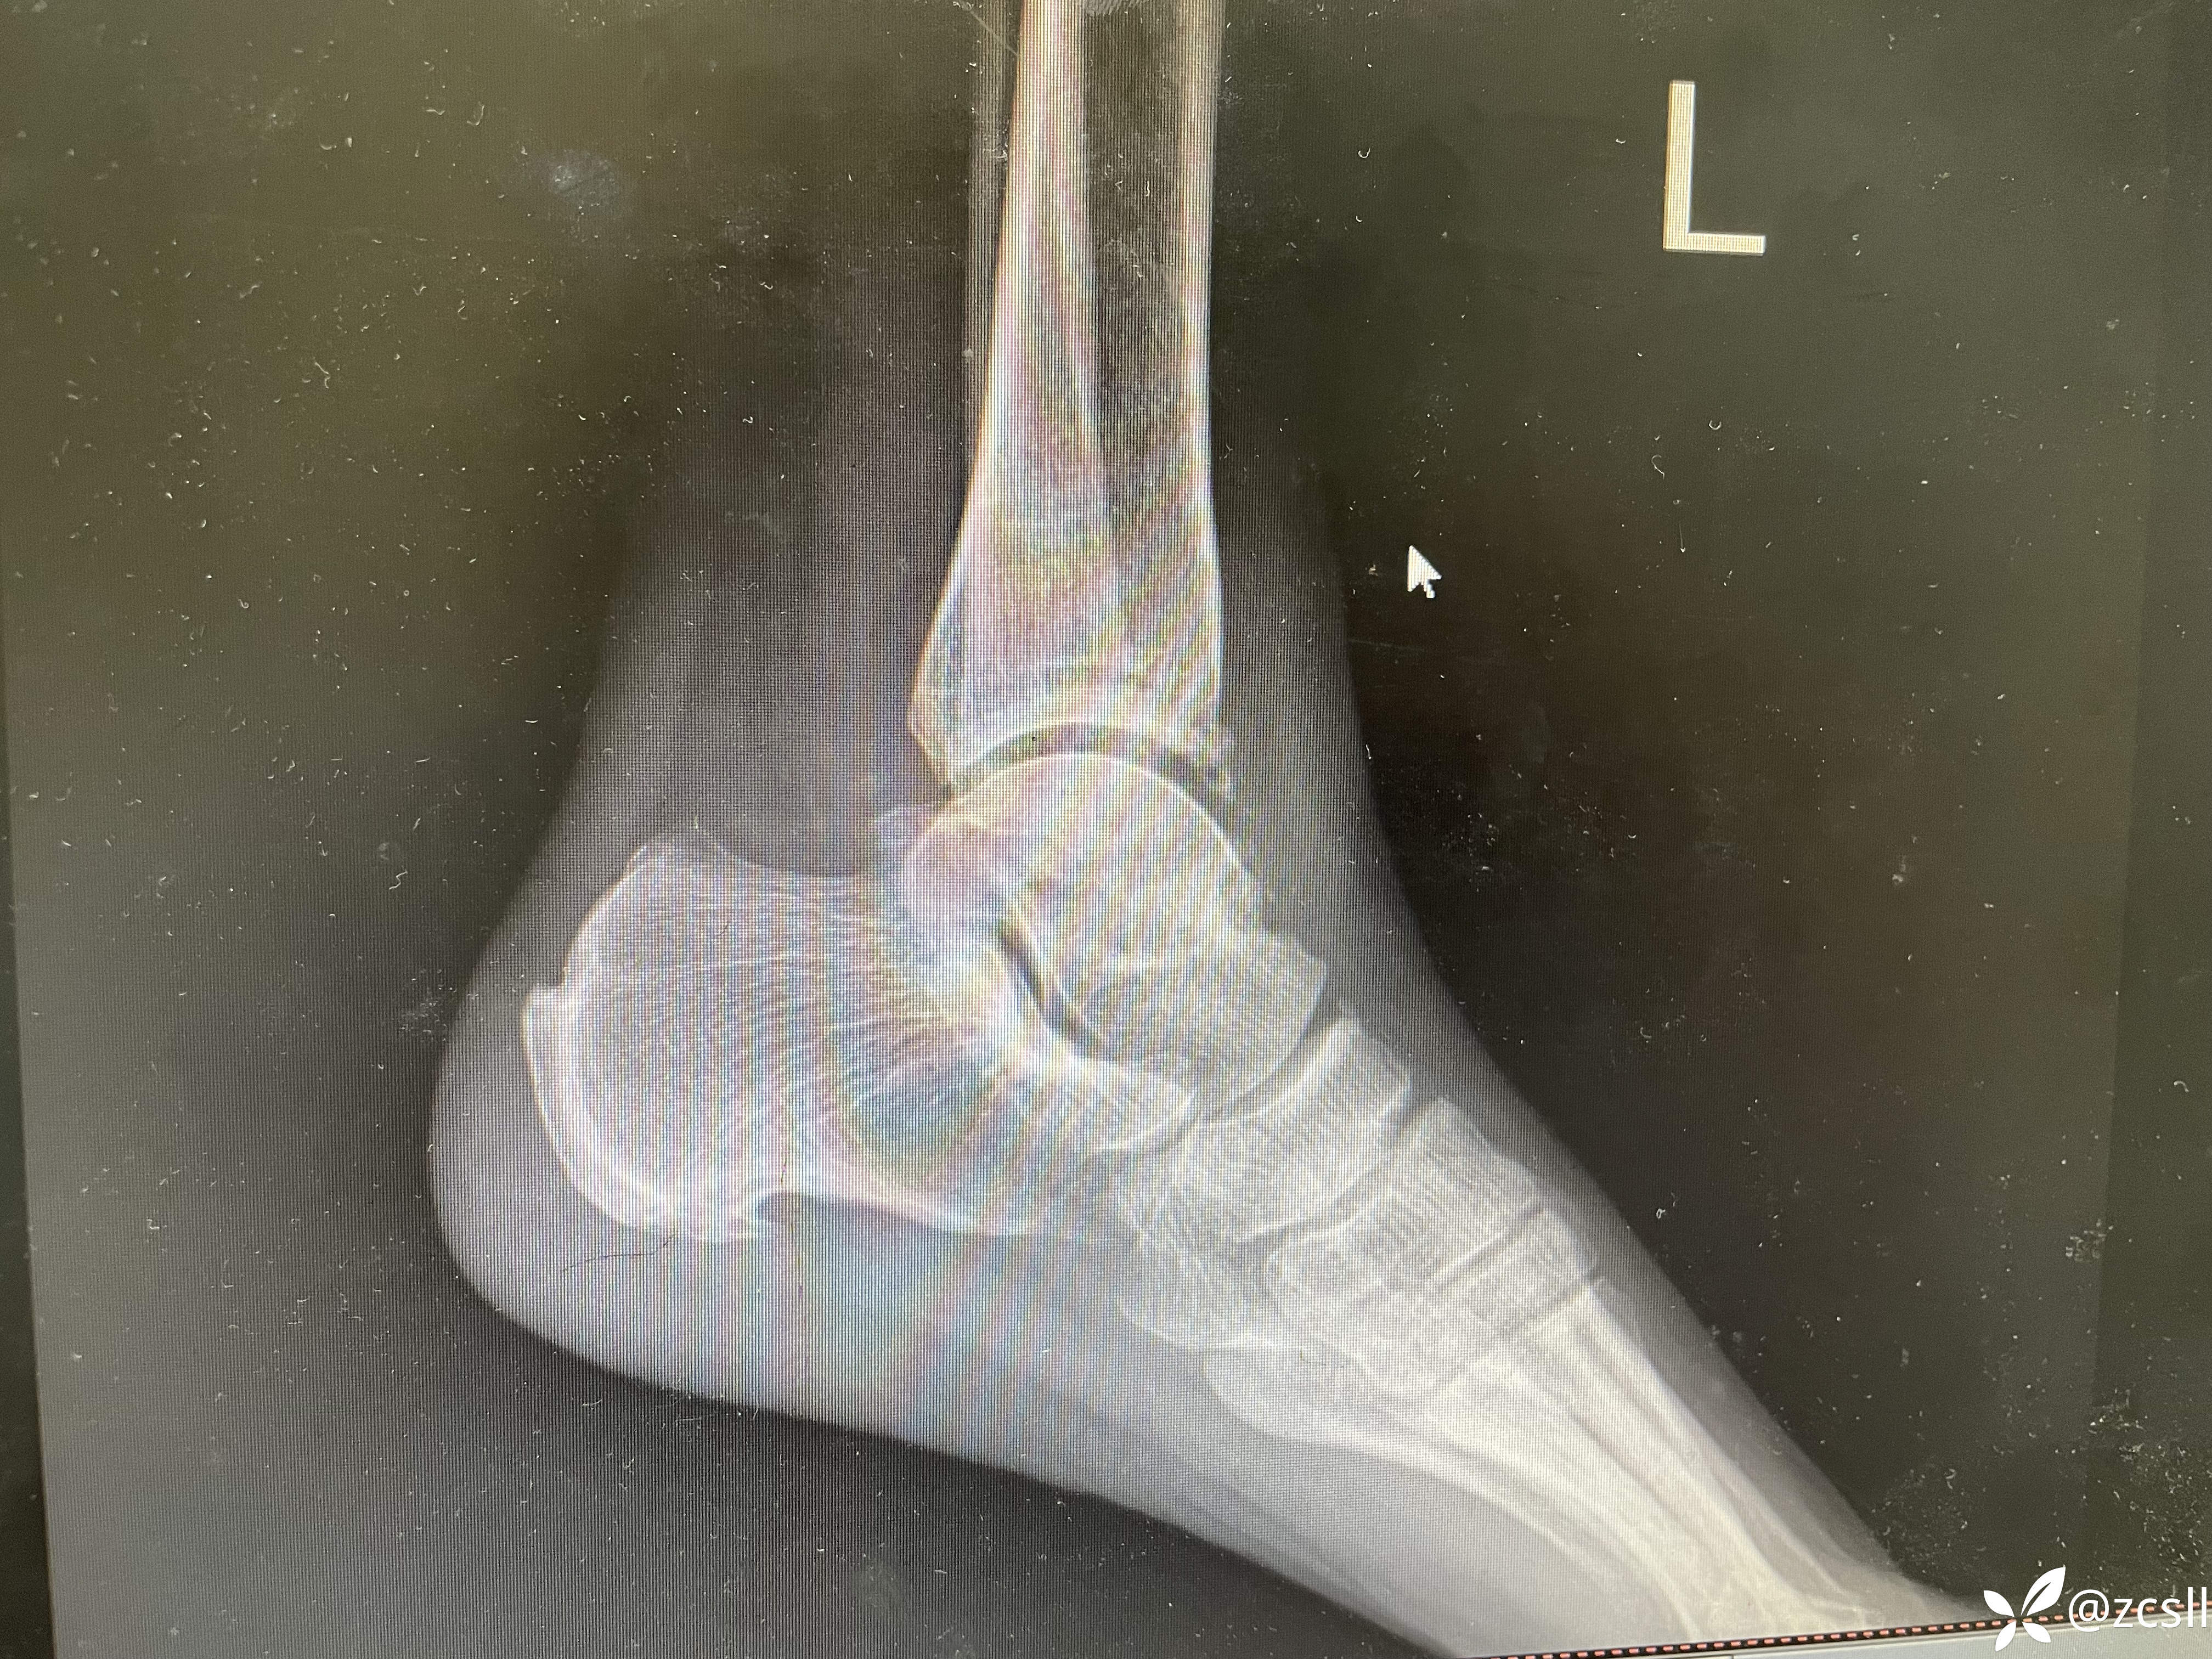

女性,59岁,双踝关节疼痛,局部无红肿,关节彩超提示双轨征,晶体性关节炎不排除。完善踝关节x片提示痛风石?该患者无高尿酸血症病史,入院查血尿酸410。针对这个患者,到底是真痛风还是假痛风呢?期待,路过的同仁能帮助分析分析。